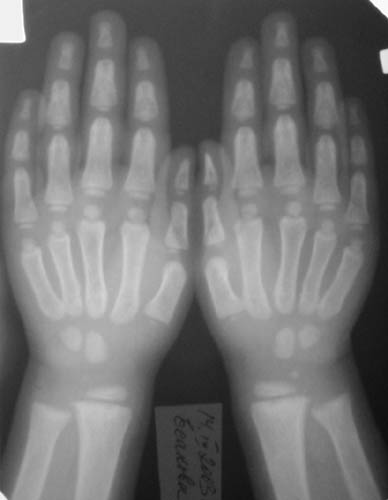

Таз Кисти Голени

Девочка, 3 года 11 мес. Дз: Фосфатдиабет (витамин Д-резистентный рахит).

Жалобы на задержку роста. Общие анализы крови и мочи без особенностей. Биохимический анализ крови: билирубин 7,7, АЛТ 0,30, общий белок 73, креатин 0,061, щелочная фосфотаза 49%мл/г, K+ 4,4, Na+ 139, Ca++ 0,93, Ca общий 2,5. УЗИ органов брюшной полости: норма, печень увеличена, паренхима однородна, сосудистый рисунок сохранен. Рентгенологический возраст 2 года, хронологический возраст 4 года. Ранее рекомендована ЛФК, витамины, видеин. Рекомендации по лечению? Заранее благодарен! С уважением, А.В.Владзимирский Донецкий НИИ травматологии и ортопедии